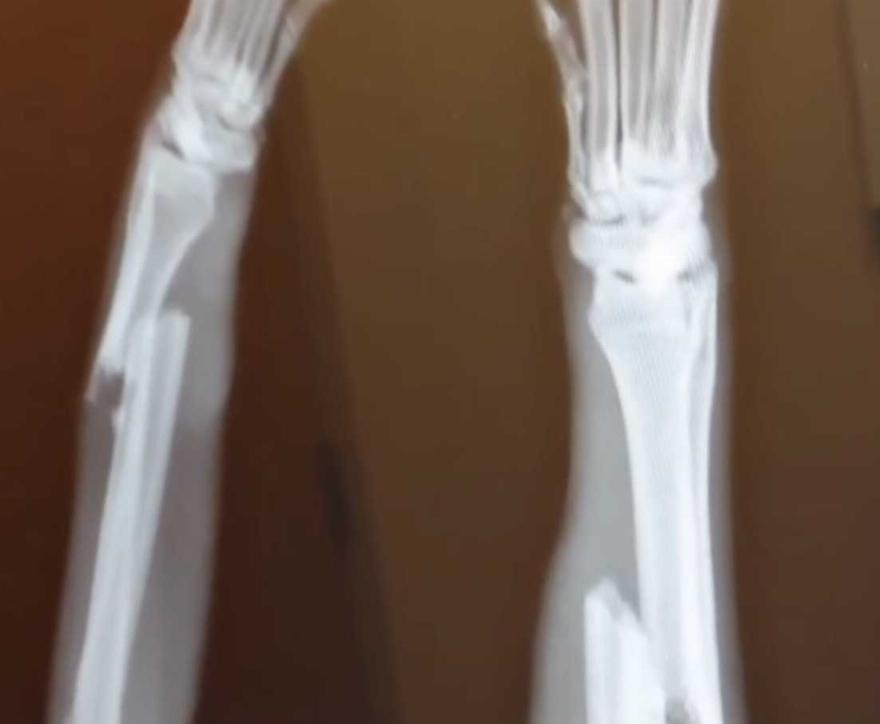

Μια συγκινητική ιστορία έρχεται στο φως της δημοσιότητας, με ένα σκυλάκι το οποίο όταν κατέφθασε έξω από το δασοφυλακείο είχε σπασμένα πόδια.

Το σκυλί με όνομα Ρέιντζερ κατευθύνθηκε προς το κτηνιατρίο ώστε να του δώσουν τις πρώτες βοήθειες και να του περιποιηθούν τα τραύμα του.Οταν κατέφθασε το πρώτο πράγμα που έκαναν οι γιατροί έψαξαν να βρουν αν υπάρχει τσιπ κι σε ποιο όνομα είναι αλλά δυστυχώς δεν υπήρχε.